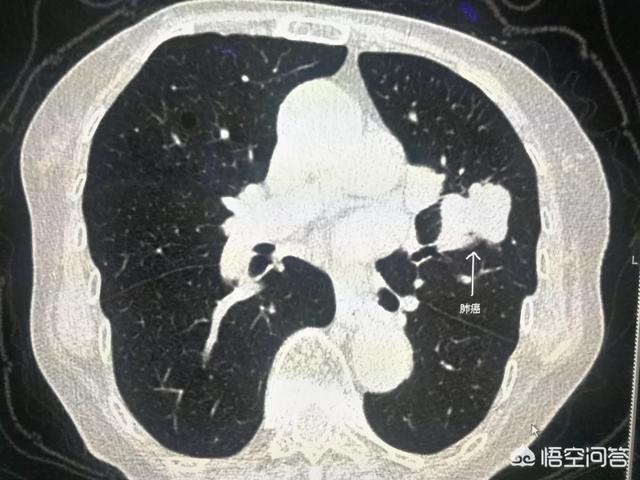

CT所示肿块为左肺癌。依据:肿块,分叶,支气管截断。

回到,问题提的肺癌,何时CT确诊。其实简单一句话,CT单靠影像表现无法确诊肺癌。

很多人习惯说,胸片看不清这个肺结节是不是癌,做个CT确诊下,这个表述是错误的,包括在CT在内的影像学检查对绝大多数的病都是确诊不了的。